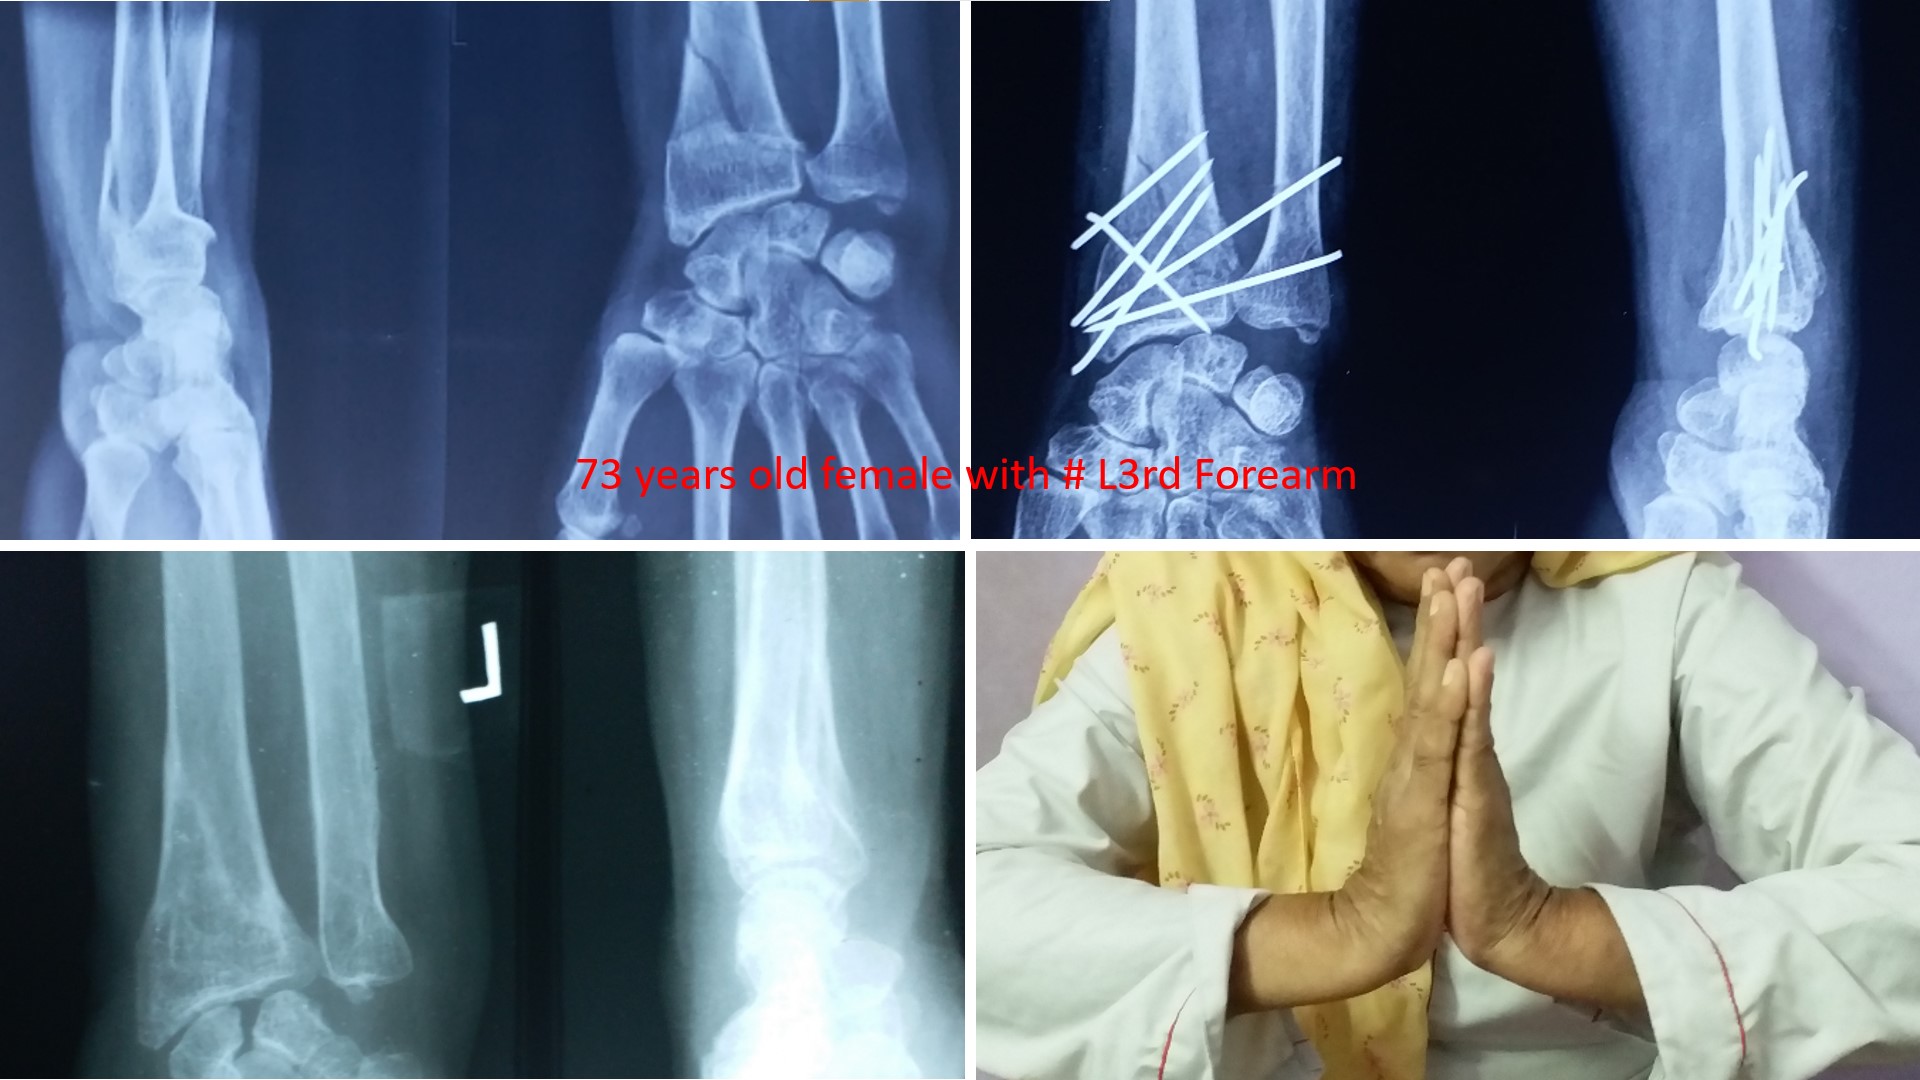

FRACTURE LOWER 3RD FOREARM